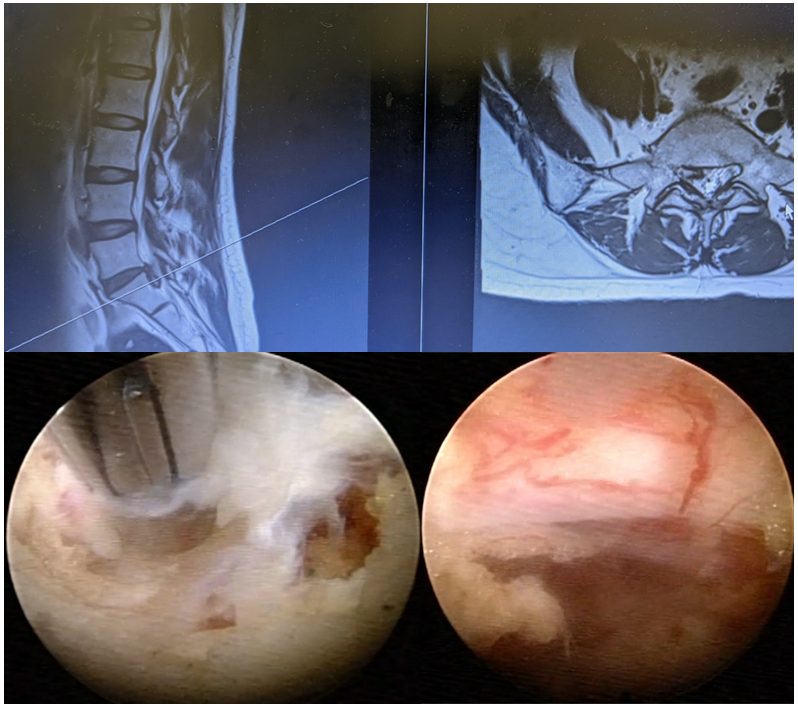

圖四

此高度向下游離的椎間盤(上圖),即使使用開放性手術或是顯微鏡手術都被認為是相對難度比較高的。藉由熟練的脊椎內視鏡手術醫師以及最新型的器械,仍可安全有效的清除游離之椎間盤。下圖左為內視鏡下摘除椎間盤的過程。下圖右為減壓後之神經根。